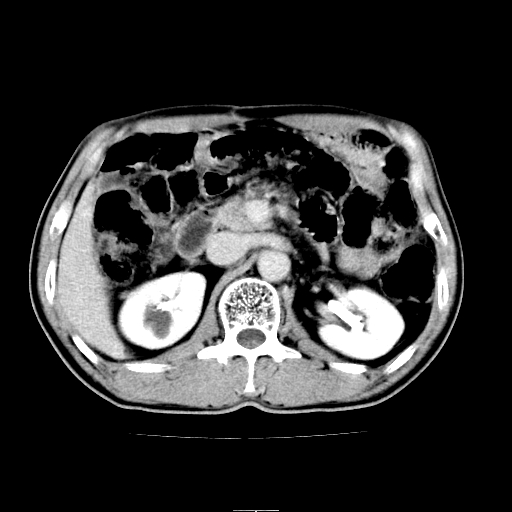

患者男,64岁,胃癌术后三个月,无明显不适。请讨论一下胰头前方小圆形低密度影为淋巴结还是肠管?

增强第6幅图上有气液平相通,是肠管,右肾低密度灶形态不规则似有壁结节,不除外转移.

应该考虑是肠管,理由1、平扫和增强对比,形态和内部的密度有明显改变。2、增强图片可见明显气液平面。

是肠管影。还有右侧肾盂旁囊肿。

病灶确实存在,请看以下2幅图片:

另外,胰腺体部密度在平扫和增强时均不太均匀,似有数个小的囊状低密度区存在。不知道增强时其他期如何?应该高度警惕为转移性病变。

胰头右侧低密度影卡考虑为肠管;胰头前部低密度影,增强环形强化,结合临床首先考虑转移灶,其次考虑淋巴结结核(中心干酪性坏死)。

支持肠管,建议口服5%泛影葡胺5/10分钟扫描